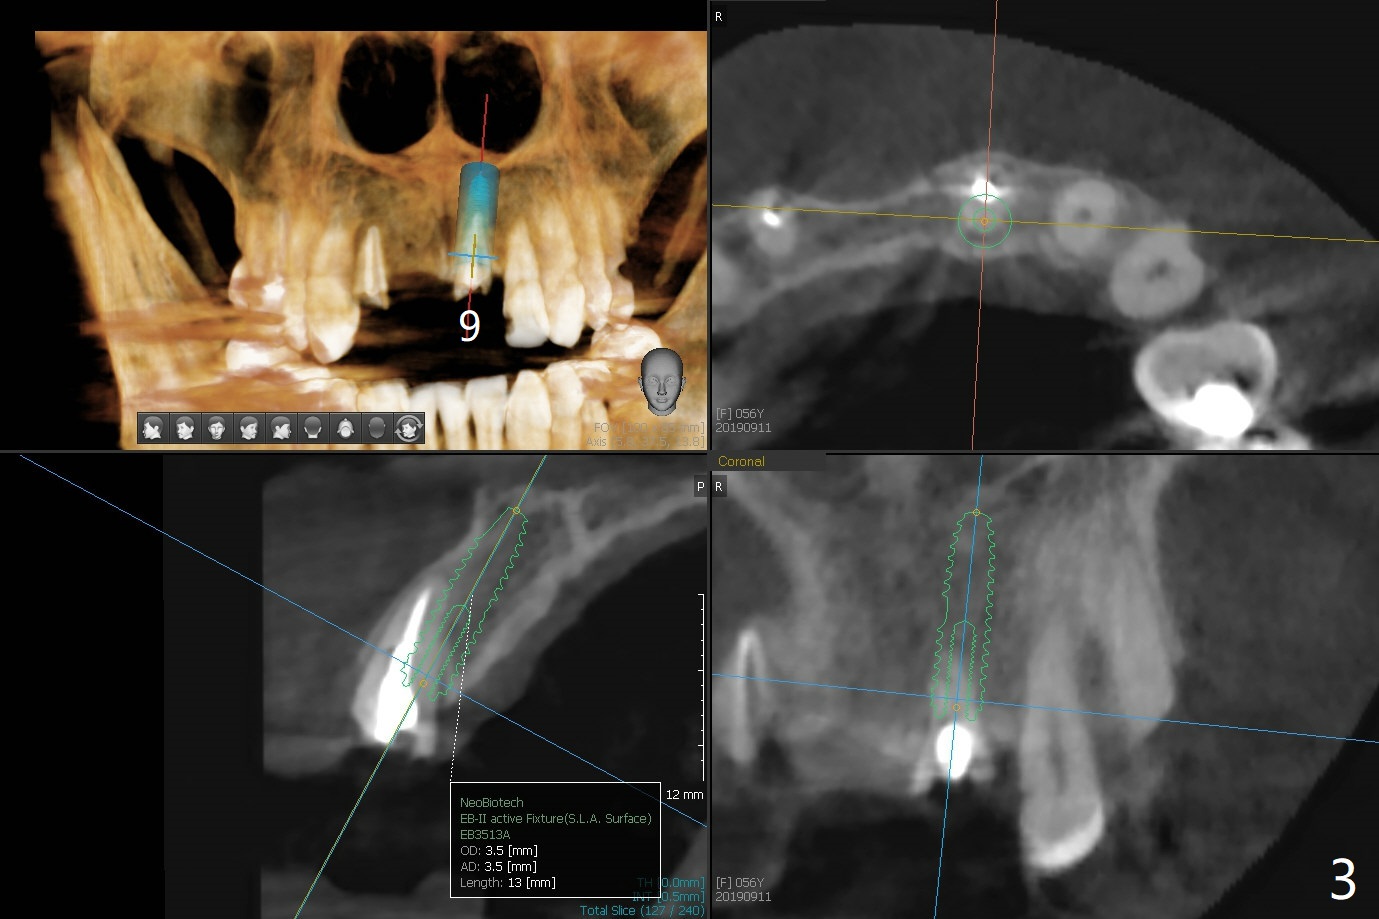

A 56-year-old woman without much posterior support has fractured #7-9 FPD (Fig.1). Since the bone at #7 is thinner buccopalatal than that of #9 (compare Fig.2,3), a shorter implant will be placed at #7 with an angled abutment. External sinus lift is required with PRFx2 before implantation at #14 and 15 (Fig.4). For #19 with the narrow mesiodistal space, a narrow implant is indicated (Fig.5).